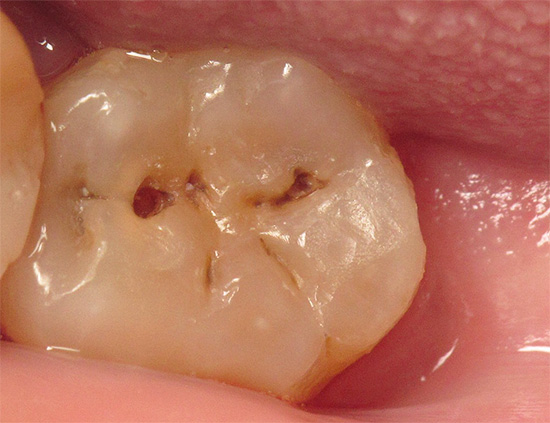

Una fotografia di un dente con una cavità profonda e cariata, che in qualsiasi momento può causare pulpite: